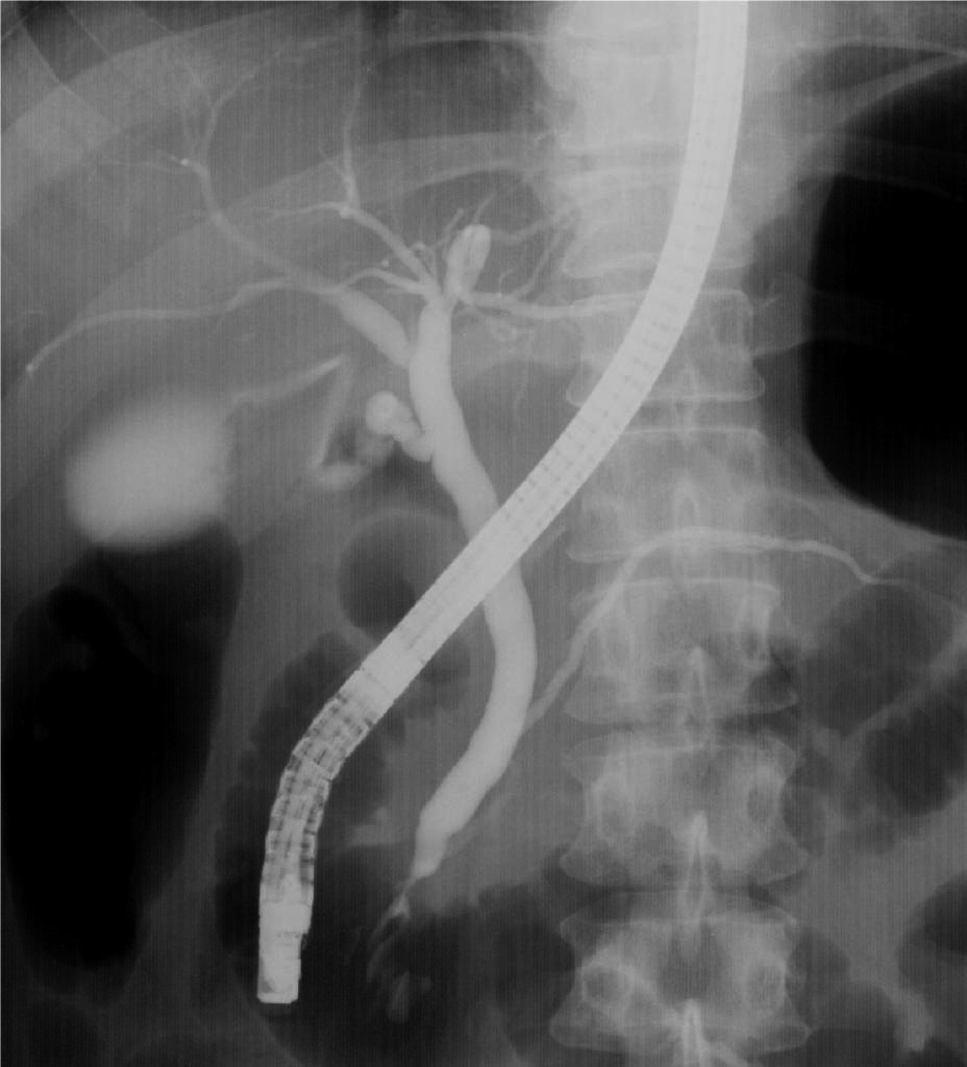

Q3) ERCP検査と胃カメラ検査と何が違うのですか?

![]() |

A3) どちらの検査も内視鏡を挿入する検査ですが、胃カメラは胃の壁を観察して病変を見つける検査で、ERCPは内視鏡の側溝から細い管を使って、胆管や膵管を造影して観察する検査です。 |